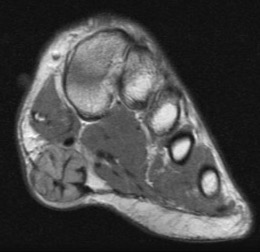

MRI

Focal oval shaped lesions within the plantar fascia